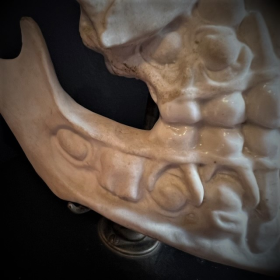

Human jaws in porcelain mounted on a blackened wooden base

Anatomical dental model for dentists

19th century

Human jaws in porcelain mounted on a blackened wooden base - Napoleon III type

Anatomical dental model for dentists of the lower skull from the 19th century

There is a small lack at the nasal level, when viewed from the front on the right side.

I had never seen an anatomical model in porcelain before.

Model for dental surgeon or stomatologist?

Nice piece

What is original is that the whole piece is made of unglazed porcelain, which is called biscuit, except for the teeth which are well glazed.

Diameter of the base: 15cm

Total height: 15/16cm

Original metal fixation system

Human jaws in porcelain mounted on a blackened wooden base

Anatomical dental model for dentists

19th century